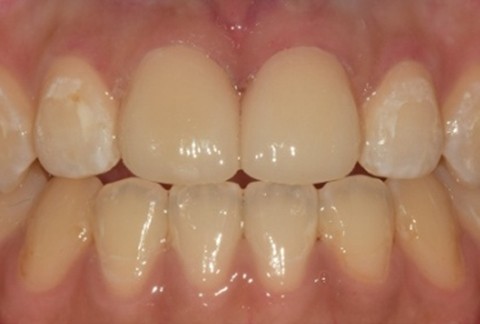

임플란트-전후사진